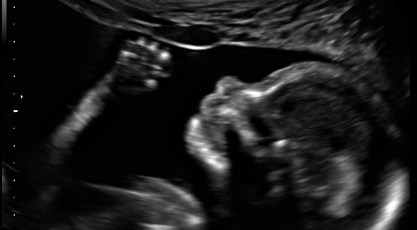

Okay, everyone in my life knows this by now, but…it’s a boy! I was not surprised for some reason, even though I kept imagining having a girl. After finding out, my grandma said she knew it was a boy from the way I’m carrying. Hmm. I think it’s a good thing I’m having a boy, because I kind of wanted a girl to live out my perfect girl life fantasies and a boy just won’t have that crap put on him! Except maybe by his dad. I babysat so many wonderful boys, too. And why would I want to fight with a teenage girl someday? With a boy, though, I worry more about him doing stupid stuff, especially when he starts driving. Even the most responsible, cautious guys I know were into things like racing each other on two-lane highways with lots of curves and steep drop-offs. Oh, joy!

My parents got to attend the ultrasound, which was fun! Everything was normal except they never saw the stomach empty and wanted me to return in three weeks to look for that. I ended up deciding not to because I think I pay like $80 for the ultrasounds, I’m somewhat concerned about possible risks of too many ultrasounds, and I haven’t been able to figure out what sort of problem they’re actually concerned about and it sounds like there’s nothing that would be done before the birth if there is a problem, anyway. Also from what I’ve read it sounds like it might have been too early to necessarily see stomach emptying in the amount of time we were there. At my next prenatal visit, the midwife said she’d never seen that comment on an ultrasound report before and didn’t have any advice either way. So I’m just not going to worry about it! But I do wish I had asked more questions when I was there with the perinatologist who told me to go back. Live and learn…